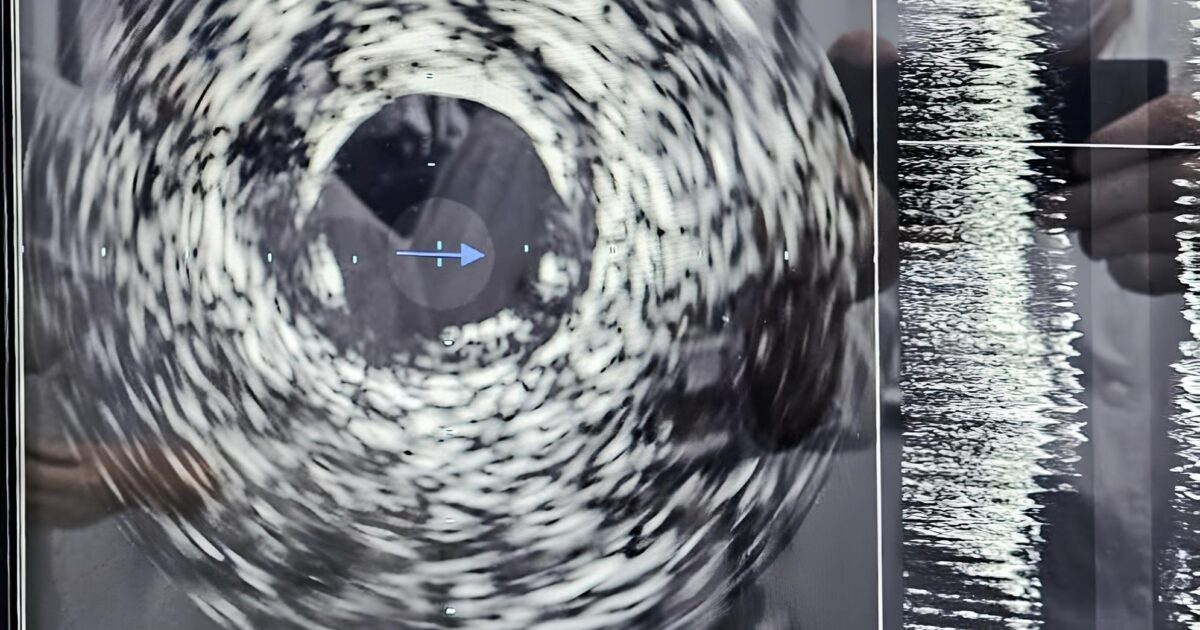

В Кирове начали применять внутрисосудистое ультразвуковое исследование

В отделении рентгенэндоваскулярной диагностики и лечения КОКБ проведены с её применением провели первые успешные операции на сосудах сердца. Ультразвуковой датчик имеет диаметр всего 1 мм, он вводится хирургом в артерию и позволяет получить необходимую информацию всего за 5-7 минут. В том числе о степени сужения сосуда (с точностью вычисления диаметра до 0,1 мм), о составе атеросклеротической бляшки. Врачи могут выбрать наилучший коронарный стент и оценить восстановление кровотока для более точного определения тактики лечения.

Главный врач КОКБ Вадим Ральников подчеркнул, что подобное оборудование доступно лишь в крупных медицинских центрах с высокой хирургической активностью. Ежегодно в отделении рентгенэндоваскулярной диагностики и лечения КОКБ проводится более 7000 хирургических вмешательств, преимущественно при остром коронарном синдроме.

Инновационная технология стентирования коронарных артерий способна продлить жизнь пациентам, предотвратить серьезные изменения в миокарде и избежать необходимости открытого хирургического вмешательства. Использование малоинвазивных методов лечения ишемической болезни сердца соответствует ключевым задачам национальных проектов «Здравоохранение» по увеличению ожидаемой продолжительности здоровой жизни.